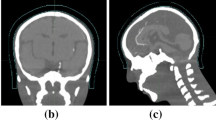

Supplementary Figure 1. CT scans of example patients using traditional vs 3D printed boluses. Supplementary Table 1. Measurements of maximum air gaps between bolus and skin for patients with anterior scalp malignancies.